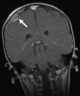

Neuroblastoma metastasis

Neuroblastoma (NB) is a type of cancer that forms in certain types of nerve tissue. It most frequently starts from one of the adrenal glands but can also develop in the neck, chest, abdomen, or spine. [Source: Wikipedia ]